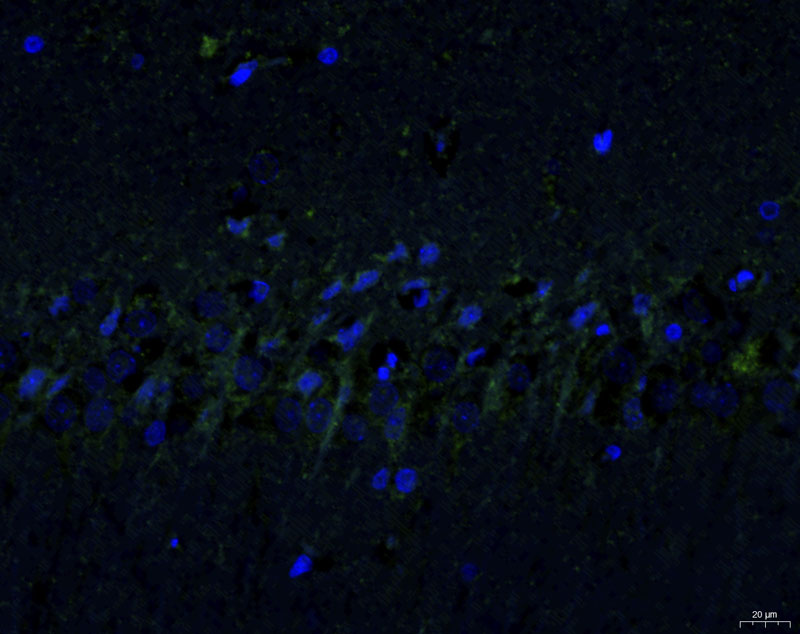

模型組1-3-40X